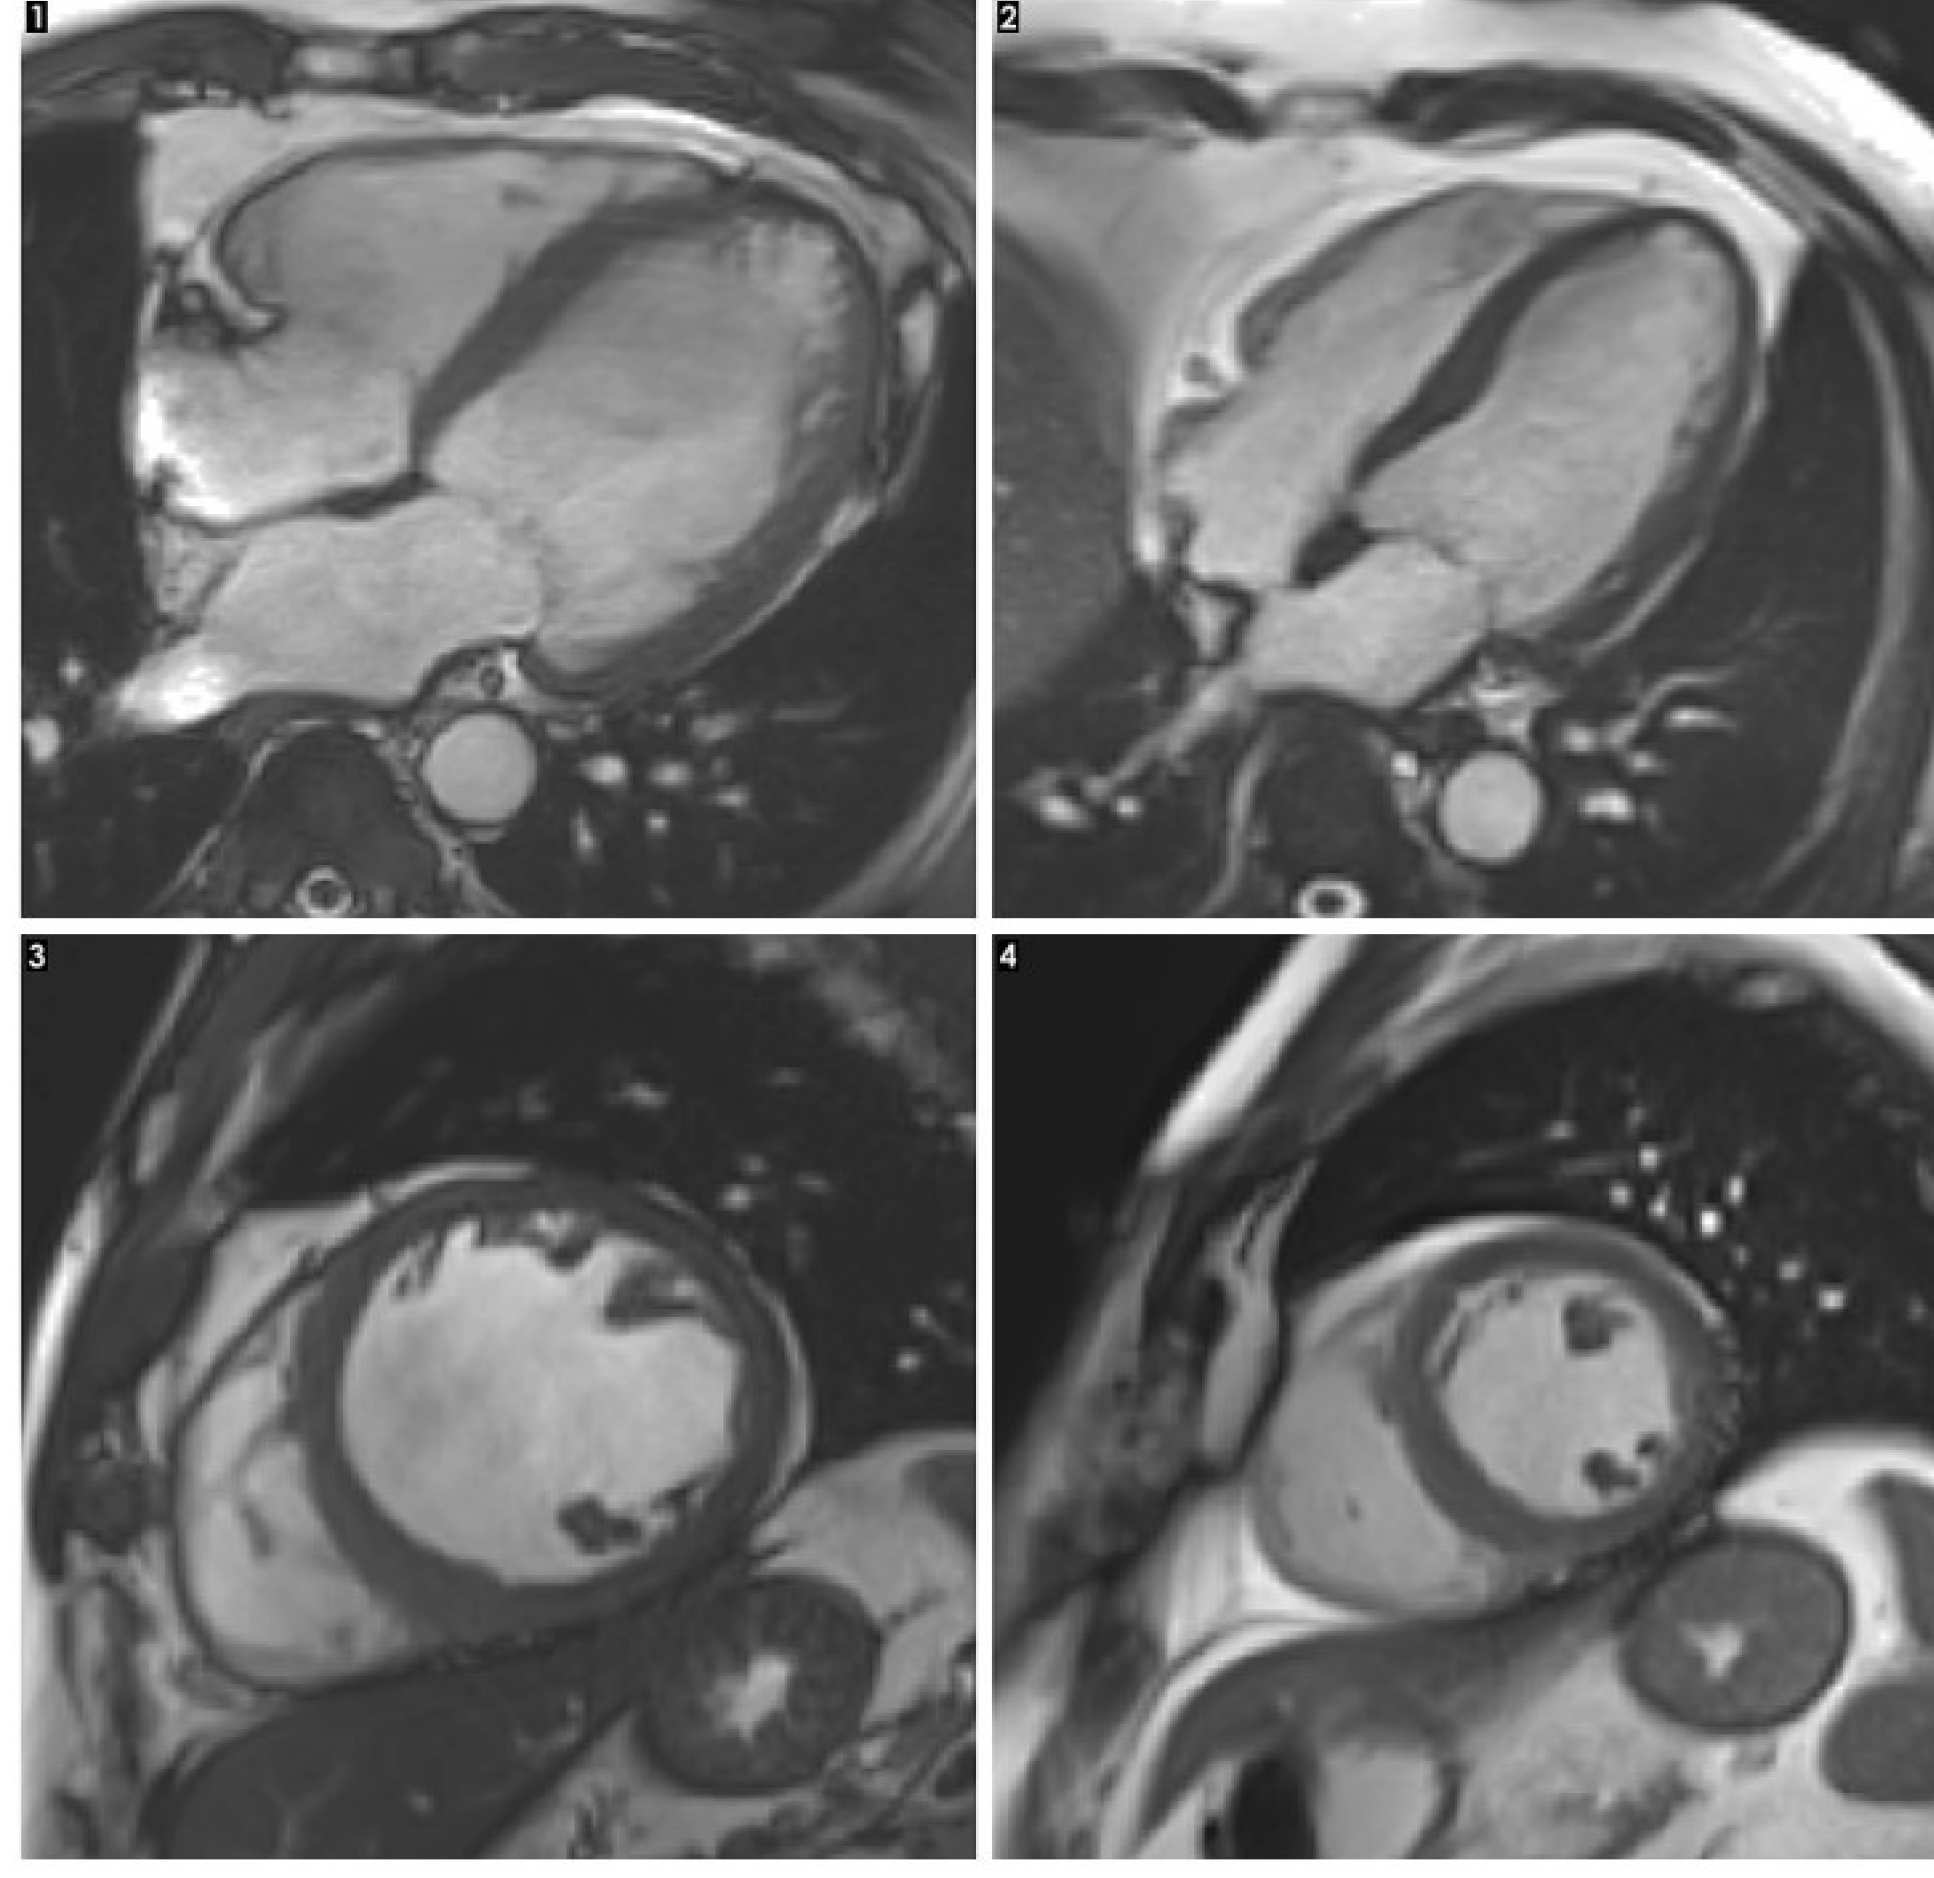

An MRI scan of a heart with alcoholic cardiomyopathy (left) compared with a healthy heart (right)An MRI scan of a heart with alcoholic cardiomyopathy (left) compared with a healthy heart (right)

1.      This image shows a cross-section of the length of a heart with alcoholic cardiomyopathy. The overall size of the heart is enlarged. The main pumping chamber of the heart (shown in this image as the large area towards the right of the heart) is also enlarged, with thin walls. This makes the heart less efficient.

2.      This image shows a cross-section of a healthy heart, where the main pumping chamber (called the left ventricle) is a normal size.

3.      This image shows a heart with alcoholic cardiomyopathy, but is a cross-section through the middle of the heart, as if looking down from the ‘top’. This shows the main pumping chamber (the left ventricle) is enlarged.

4.      This image shows a cross-section of a healthy heart.

This MRI image shows a heart with alcohol cardiomyopathy, and shows the main pumping chamber of the heart (the large area at the right of the heart in the image) is enlarged.